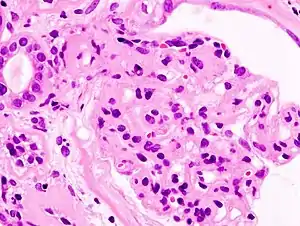

Diferentemente do que ocorre na síndrome nefrítica, na síndrome nefrótica não há invasão glomerular por células inflamatórias (glomerulonefrite), mas sim um importante comprometimento da permeabilidade glomerular, tornando os glomérulos incapazes de reter macromoléculas, como as proteínas, justificando o aumento da quantidade de proteínas na urina.

A sindrome nefrótica é frequentemente classificada histologicamente:

As causas primárias de síndrome nefrótica geralmente são as descritas pela histologia: Doença de lesão mínima, glomeruloesclerose segmentar e focal e nefropatia membranosa. Glomerulonefrite membranoproliferativa.

As causas secundárias de síndrome nefrótica possuem os mesmos padrões histológicos das causas primárias, no entanto podem exibir algumas diferenças sugerindo uma causa secundária como corpos de inclusão.